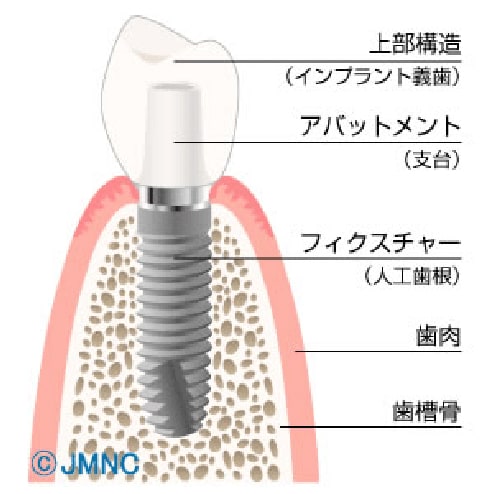

インプラント治療は人工歯根治療ともいわれ、虫歯や歯周病、歯の破折などで失った歯のかわりに人工歯根(インプラント)をアゴの骨に埋め込み、その上に支台部(アバットメント)と人工歯を装着する治療法です。

インプラントは生体と親和性の高いチタンという金属で造られています。チタンは骨と結合する特質を持っており、長年の基礎的研究からもインプラント材料として最適であることが確認されています。また、臨床統計的研究においてもチタン製インプラント治療を受けた患者さんにおいて、10年以上に渡り正常に機能しているインプラントは95%以上と、その信頼性が実証されています。